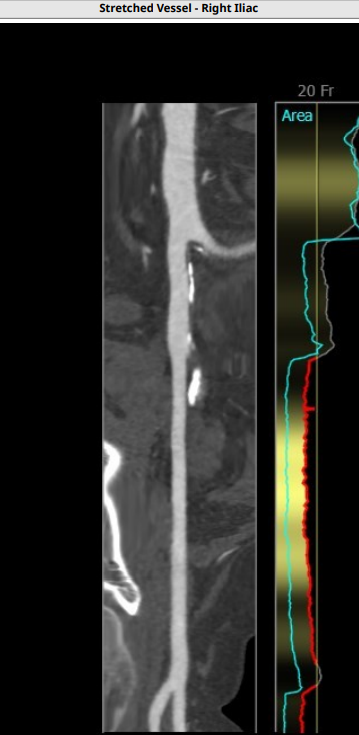

此例患者大横位Type0型二叶瓣,瓣环径23.1,LVOT22.6,Stj35.9,左冠高度11.8,右冠19.5,术前根据总体结构使用20MM球囊预扩,抓捕器辅助瓣膜通过横位结构跨瓣,术前预装VenusA23号瓣膜。

入路